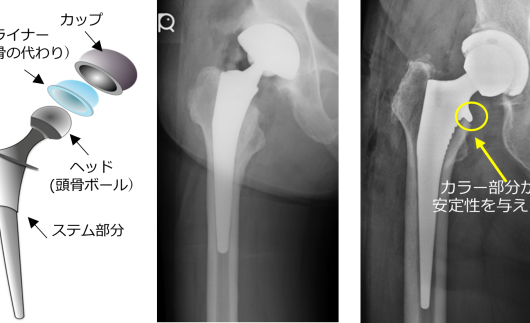

人工股関節全置換術後の骨折予防に新展開?-カラー(襟)付きHAステムの有効性に期待-